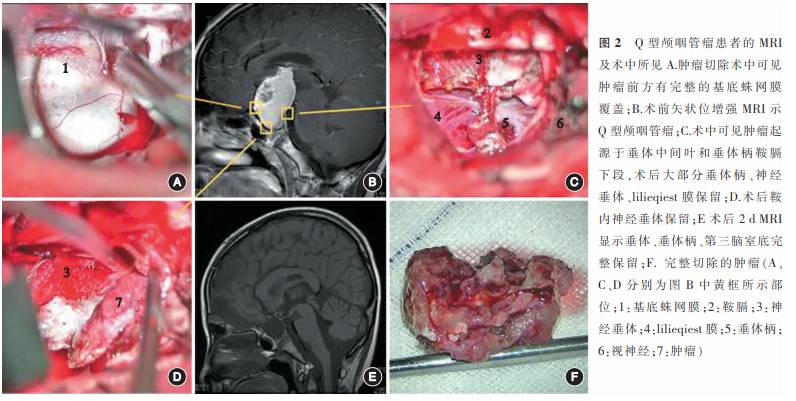

4. 手术方法及切除程度评价:手术均在全身麻醉下进行,沿肿瘤周边进行完整整块切除,主要采用前纵裂入路、经翼点入路、经额下入路、经鼻蝶入路进行手术(图2~4)。Q型肿瘤主要通过经前纵裂入路进行切除(16例,55.2%),其次采用经翼点入路(6例,20.7%)及经鼻蝶入路(7例,24.1%)。S型肿瘤主要通过经翼点入路进行切除(19例,70.4%),其次采用经前纵裂入路(5例,18.5%)及经额下入路(3例,11.1%)。T型肿瘤主要通过经前纵裂入路进行切除(52例,85.2%),其次为经翼点入路(9例,14.8%)。术后3d内行头颅MRI平扫及增强扫描,结合手术录像判断手术的切除程度:

1. 手术及病理学结果:本组病例全切除率达100%(图2~4)。117例患者中,造釉细胞型颅咽管瘤100例,鳞状乳头型17例。